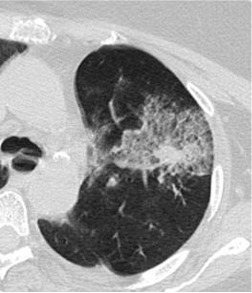

| 活检后伴有少量出血的肺小细胞肿瘤。患者离开前至少左侧卧2小时。Little cell’s tumor of the lung with minor haemorrage。This patient must stay at least 2 hours laying in left decubitus before leaving the station。 | |

题外话:这种胸膜下结节,尽可能有角度的进针(通过一段肺组织)。操作者选择直接经病变的基底部进入病变,可能会减少气胸的发生,但潜在增加种植转移可能。

肺肿瘤(腺癌)穿刺后少量出血和气胸。患者需要静躺数小时,离开前需要重复胸部CT扫描 Tumor of the lung (adenocarcinoma) with minor haemorrage and a small pneumothorax.This patient should be kept stationary for some hours and be submitted to cheat CT scan before leaving